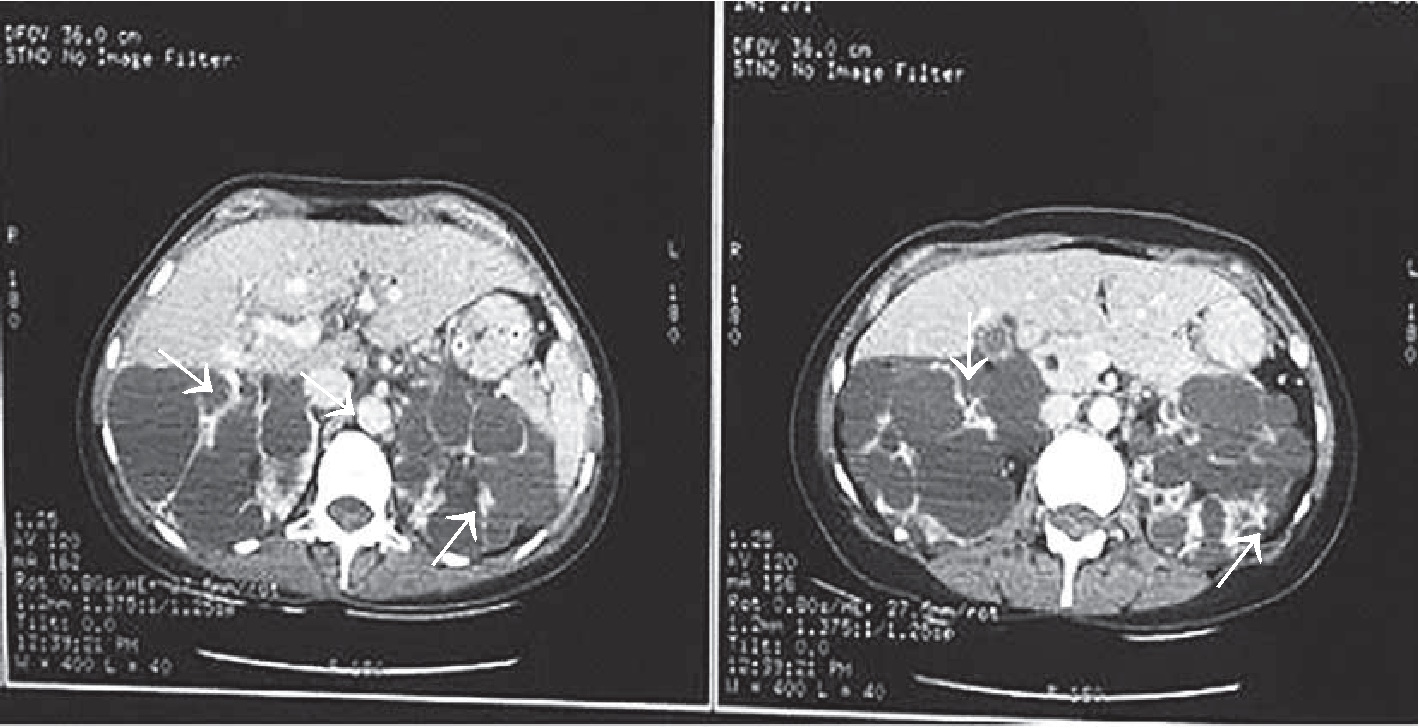

26.01.2019 г. для исключения патологии со стороны центральной нервной системы, уточнения причин угнетения сознания с развитием судорожного синдрома, исключения отека легких, аспирационного синдрома, а также исходя из наличия в анамнезе поликистоза почек пациентке была выполнена КТ головы (рис. 1), груди (рис. 2), живота (рис. 3), по результатам которой отмечалось минимальное субарахноидальное кровоизлияние в височной доле справа; имелись признаки аксиальной дислокации 1 – 2 степени. Объёмных образований, гематом в веществе головного мозга не выявлено. Пристеночное утолщение слизистой оболочки в лобной пазухе, клетках решетчатого лабиринта, обеих верхнечелюстных пазухах и основной пазухе слева с наличием в последней минимального уровня содержимого. Диффузная интерстициально- альвеолярная инфильтрация лёгочной ткани с обеих сторон с наличием небольшого количества жидкости в плевральных полостях, вероятно, как проявления отёка лёгких. В зоне сканирования поликистоз печени, почек.

Рис. 1. КТ головы. Определяются признаки минимального субарахноидального кровоизлияния в височной доле справа, аксиальной дислокации 1 – 2 степени